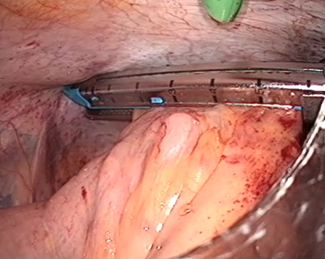

カッターとホッチキスが合体したような器械で、大腸を切り離します。

この後、お腹の一番下の傷を4cmに広げて腸を引き出し、大腸の口側をお腹の外で切り離します。

これで、病気の部分を含んだ大腸が切除されます。